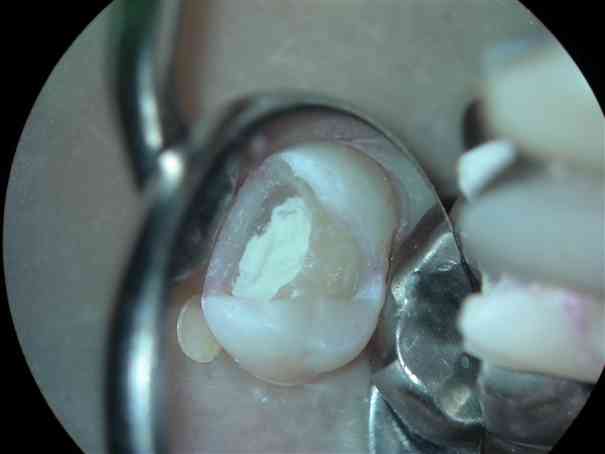

虫歯を感染に取り除くと、は本来の色になりましたが、神経が露出しそうな状態です。 |

最も神経に近い部分に慎重にPROroot MTAを入れてゆきます。これがうまくいくと、患者さまもほとんど痛みが出ることがありません。 |